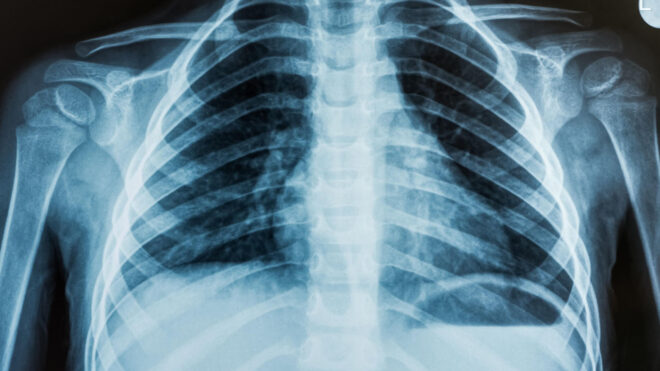

xAI imzalı üretken yapay zeka temelli ChatGPT rakibi Grok, yapılan güncelleme sayesinde artık röntgen ve MRI’ları analiz edebiliyor.

Bu gelişme hakkında bir açıklama yapan Elon Musk şunları aktardı: “Röntgen (X-Ray), PET, MRI veya diğer tıbbi görüntüleri analiz için Grok’a göndermeyi deneyin. Bu altyapı henüz erken bir aşamada, ancak şimdiden oldukça doğru sonuçlar veriyor ve ileride daha da iyi hale gelecek. Grok’un doğru analiz ettiği veya üzerinde çalışılması gereken hataları bize bildirin.” Bu işlemciler için ciddi bir sunucu gücü gerekiyor ve şirket bunun için büyük adımlar atıyor. Kaçıranlar için Elon Musk geçtiğimiz ay xAI, X, Nvidia ve diğer bazı şirketlerin desteğiyle bir araya getirilen tam 100 bin sıvı soğutmalı Nvidia H100’ün (yapay zeka eğitimine odaklanan çok güçlü GPU sistemi) görev yapmaya başladığını duyurmuştu. Elon Musk’tan konuda gelen son açıklama ise şöyle olmuştu: “Bu hafta sonu xAI ekibi “Colossus” adını verdiğimiz 100k H100 eğitim kümemizi çevrimiçi hale getirdi. Bu sistem baştan sona 122 günde tamamlandı ve Colossus şu anda dünyadaki en güçlü yapay zeka eğitim sistemi konumunda.”